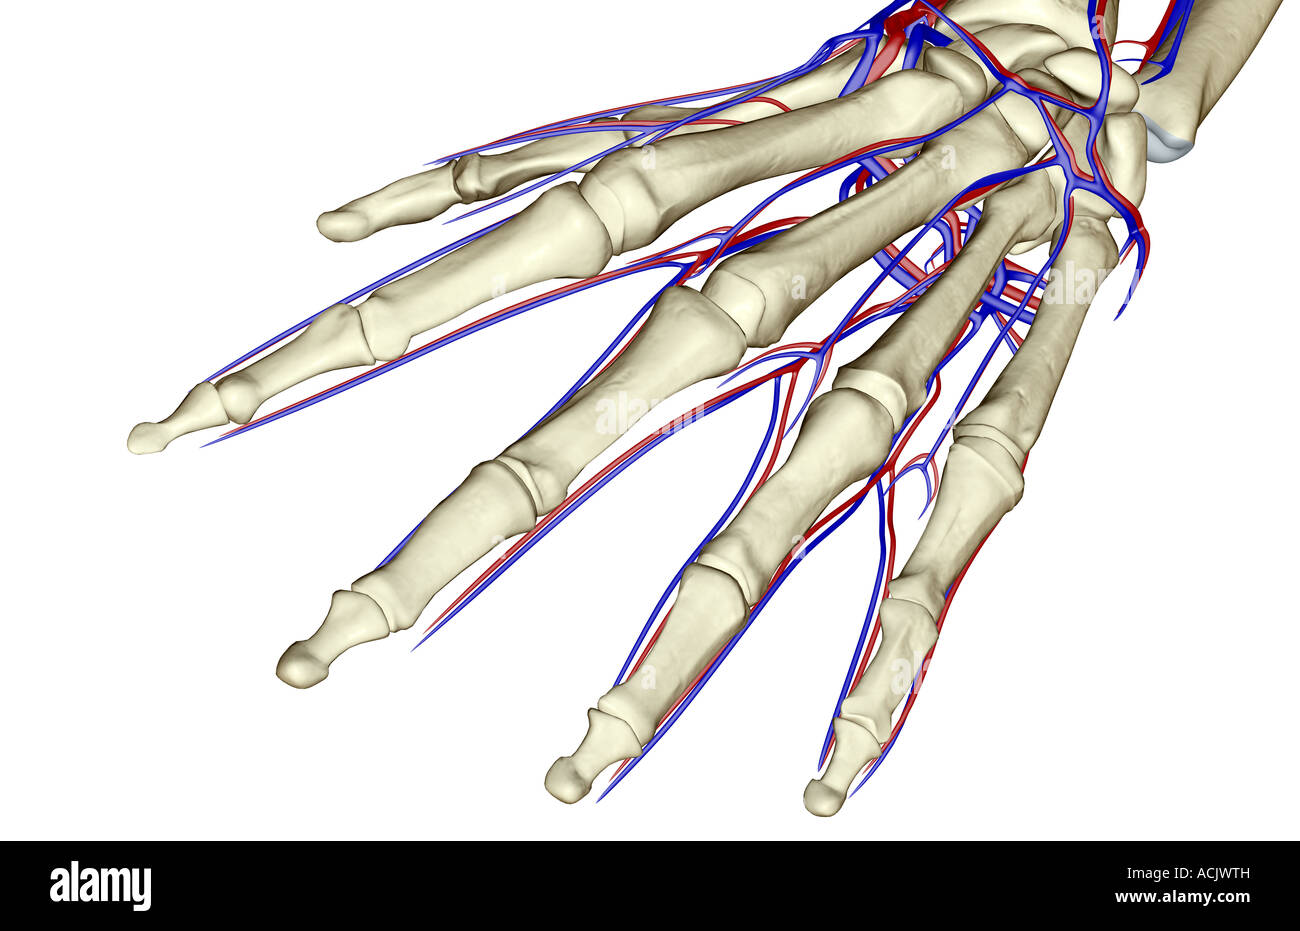

The blood supply of the fingers Stock Photohttps://www.alamy.com/image-license-details/?v=1https://www.alamy.com/stock-photo-the-blood-supply-of-the-fingers-13197438.html

The blood supply of the fingers Stock Photohttps://www.alamy.com/image-license-details/?v=1https://www.alamy.com/stock-photo-the-blood-supply-of-the-fingers-13197438.htmlRFACNCNK–The blood supply of the fingers